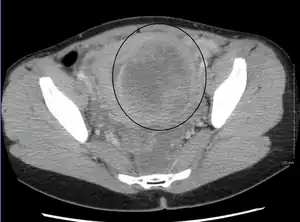

| A very large (9 cm) fibroid of the uterus which is causing pelvic congestion syndrome as seen on X-ray computed tomography | |